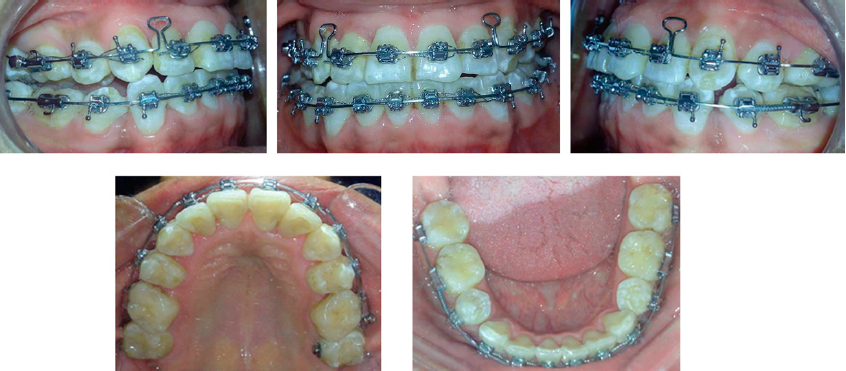

Se llevó a cabo la retracción del segmento anterosuperior inicialmente con arcos 0.019” x 0.025” SKL para lograr el cierre de espacios (Figura 5), seguido de la colocación de arcos 0.019” x 0.025” TMA en la arcadas superior e inferior (Figura 6). Al término del tratamiento se colocó retenedor fijo de canino a canino con alambre trenzado 0.175”. Al finalizar el tratamiento, se lograron clases molar y canina I en ambos lados, cierre de espacios, buena intercuspidación y alineación y nivelación dental, logrando así contribuir a mantener la salud periodontal (Figura 7). Asimismo, los ejes axiales de los incisivos mejoraron al igual que la topografìa ósea como puede observarse en las radiografías finales (Figura 8).